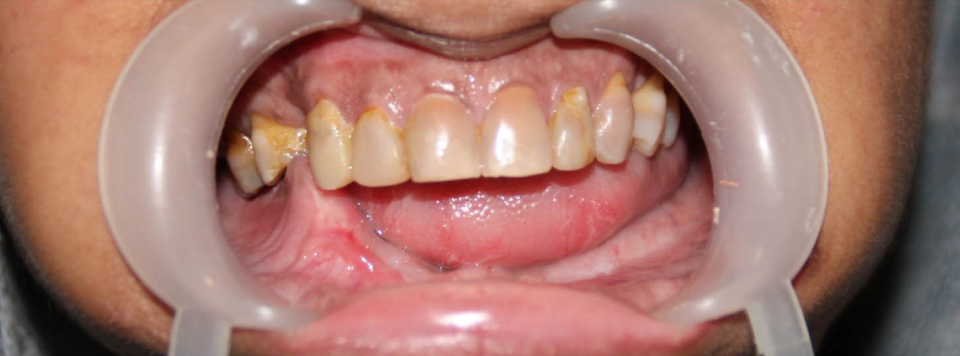

Complex Implant Rehabilitation

Complex dental implant rehabilitation is a highly effective solution for patients with extensive dental issues.

Such as severe bone loss, multiple missing teeth, cases involving tumor resection and reconstruction with vasculised bone grafts, gun shot injuries, with cleft lip and palate, jaw necrosis, post cancer oral rehabilitation.